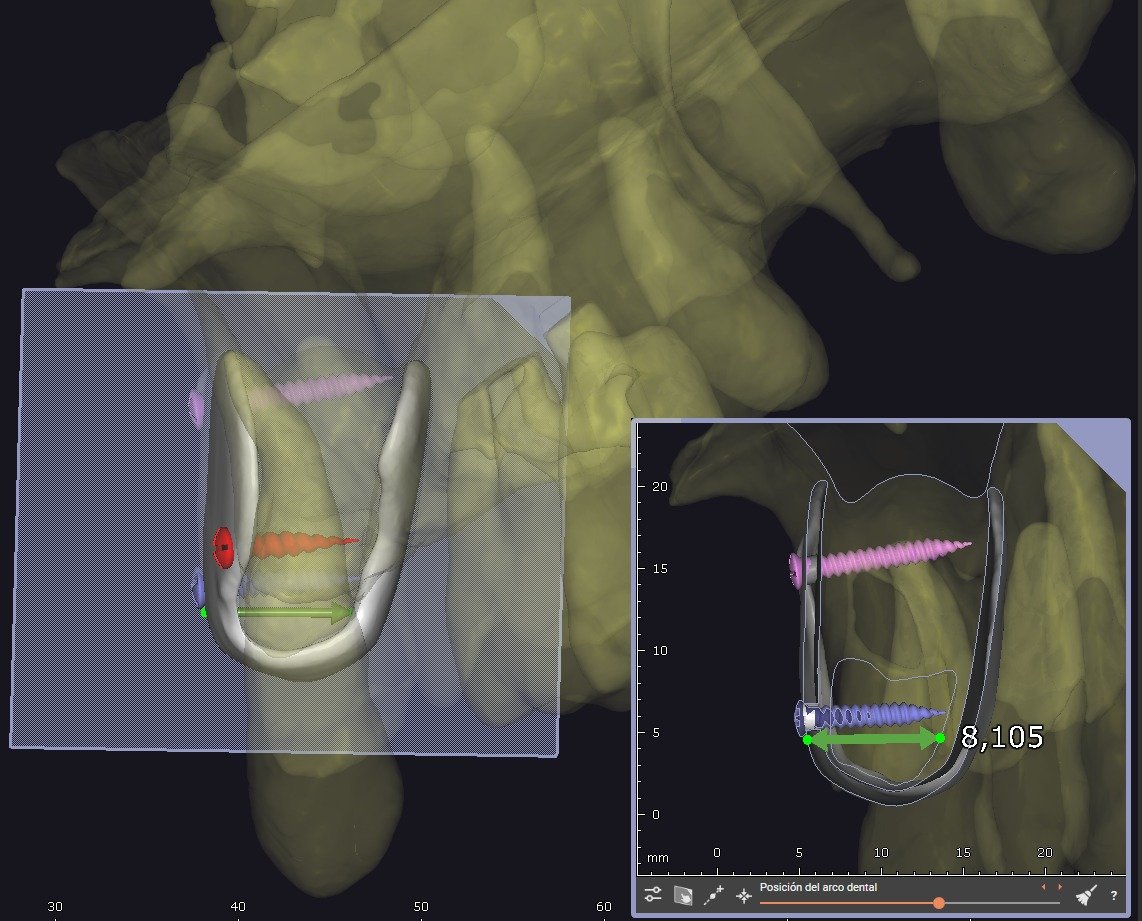

• BlueSkyPlan: diagnóstico, segmentación y análisis del defecto.

• Exoplan / Exocad: diseño digital aplicado a la regeneración.

• Segmentación ósea y dental.

• Generación del defecto virtual.

• Control tridimensional del volumen a regenerar.

• Planificación de tornillos de fijación:

• Número

• Posición

• Angulación